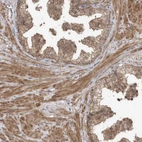

Immunohistochemical staining of human testis shows moderate nuclear positivity in Leydig cells.